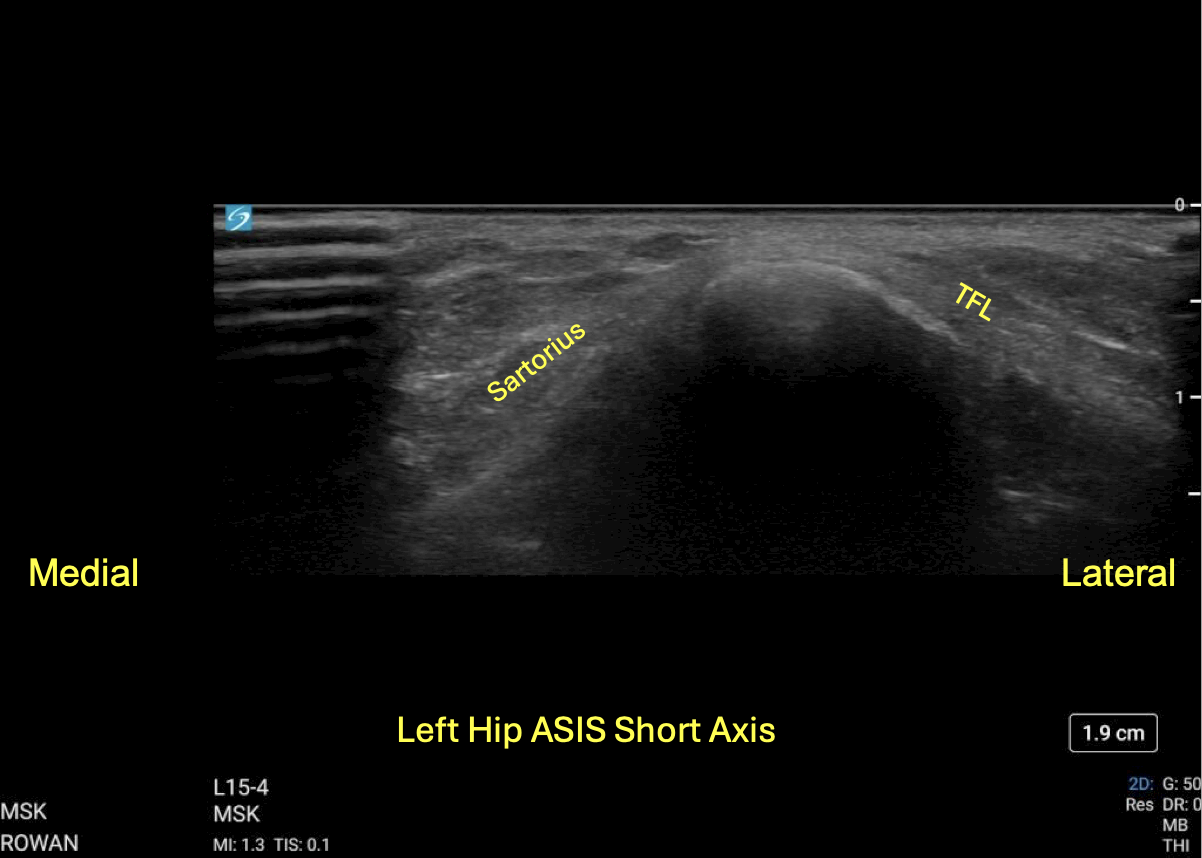

An unlabeled short axis view of the left (unaffected) ASIS.

A labeled short axis view of the left (unaffected) ASIS.